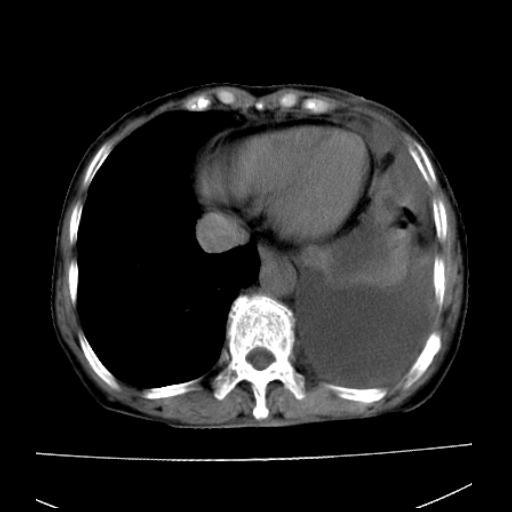

以下是引用随光逐影在2010-3-24 19:15:00的发言:[br]结合病史,考虑双肺及纵隔淋巴结多发转移、左侧胸膜转移并左侧大量胸水,左下肺膨胀不全。

以下是引用zxl51642在2010-3-24 18:49:00的发言:[br]结合乳腺癌术后病史,考虑双肺及纵隔淋巴结多发转移、左侧胸膜转移并左侧大量胸水、左下肺膨胀不全。